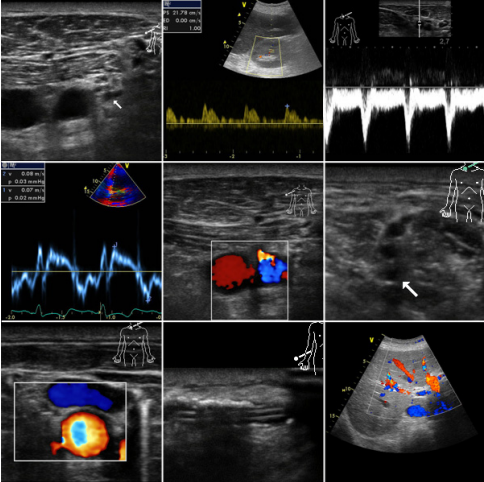

Der Einsatz von Ultraschallgeräten zur Diagnostik sowie Intervention ist mittlerweile aus dem anästhesiologischen und intensivmedizinischen Alltag nicht mehr wegzudenken. So ist es verständlich, dass die Ausbildung in der Ultraschalldiagnostik und der ultraschall-gesteuerten Punktionen für Anästhesistinnen und Anästhesisten eine wachsende Bedeutung einnimmt. Dies spiegelt sich auch in den Fachgesellschaften wieder, die der Ausbildung einen immer höheren Stellenwert beimessen.

Aus dieser steigenden Bedeutung der Sonografie für Anästhesisten und Intensivmediziner erwächst die Verpflichtung, didaktische Konzepte zu entwickeln, um eine erfolgreiche Vermittlung des komplexen Wissens zu gewährleisten. Der inhaltliche Rahmen ist durch den Anforderungskatalog der DEGUM (Deutsche Gesellschaft für Ultraschall in der Medizin) vorgegeben. Das von uns entwickelte Ausbildungskonzept erfreut sich seit Jahren einer großen Beliebtheit.

Wichtig ist uns eine didaktische Ausrichtung des Kurses mit einem starken Praxisbezug und einem hohen Anteil von praktischen Übungen in Kleingruppen.